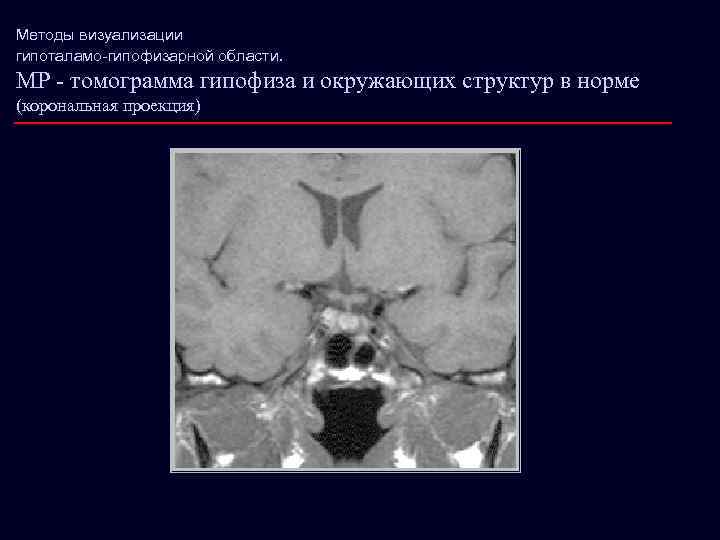

Методы визуализации гипоталамо-гипофизарной области. МР - томограмма гипофиза и окружающих структур в норме (корональная проекция)